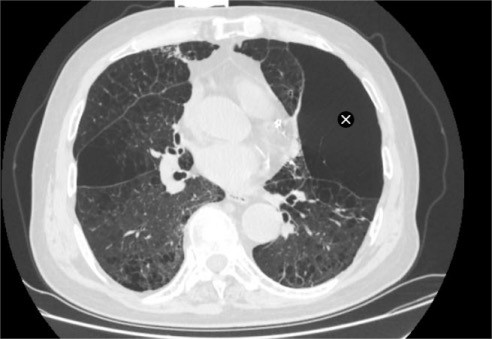

家属带着陈大爷辗转求医,来到苏州大学附属第四医院呼吸内科蒋军红主任门诊就诊。完善胸部CT检查后显示,陈大爷患有异质性肺气肿,肺部病变区域分布极不均衡,部分肺叶过度充气、丧失正常通气功能,形成“无效通气腔”,进一步加重了正常肺组织的负担,这也是他经药物治疗后仍无法缓解症状的核心原因。